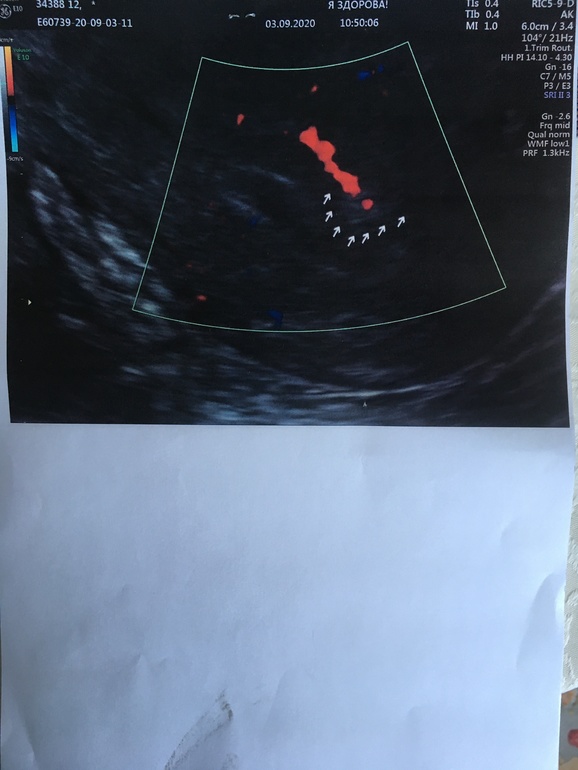

Девочки всем привет! Вступила в крио згт, все вроде бы хорошо , первое узи ре нравится , назначен дивигель , витамины , а второе узи вызывает подозрение на рубец или полип ( и сегодня я съездила на узи к Пятых, вердикт приклепляю ниже, эндометрий шикарный , ровный и трёхслойный , но вот полип скорее всего есть ! ( Расстроена очень , так как уже была настроена на перенос , но рисковать эмбриончиком не могу (. Девочки, Из насущного пожалуйста подскажите кто очень хорошо делает гистероскопию в Москве? Заранее спасибо Вам девочки за поддержку и помощь , столько много узнаю , что это мне помогает «подстелить соломинки» 🙏🏻🙏🏻🙏🏻❤️